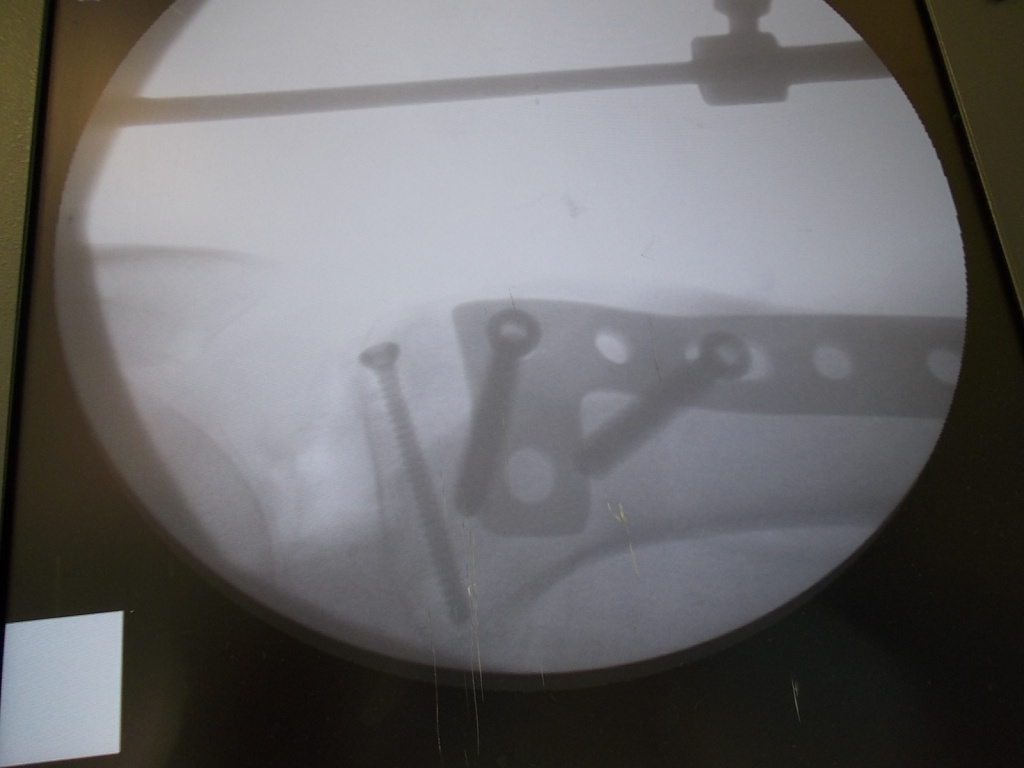

Использование материала Остеоматрикс при импрессионном оскольчатом переломе наружного мыщелка большеберцовой кости по типу Schatzker II

Использование материала Остеоматрикс при импрессионном оскольчатом переломе наружного мыщелка большеберцовой кости по типу Schatzker II.

Операция - открытая репозиция, остеосинтез большеберцовой кости опорной пластиной с костной ксенопластикой маетриалом "Остеоматрикс". На контрольных снимках в три и шесть месяцев имеется консолидация перелома, миграции фиксатора нет, имеется остеоинтеграция ксенопластического материала. Функция коленного сустава полная.